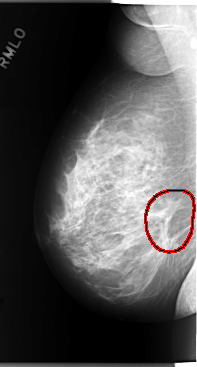

C_0101_1.RIGHT_MLO

RIGHT_MLO LINES 5872 PIXELS_PER_LINE 3152 BITS_PER_PIXEL 12 RESOLUTION 50 OVERLAY

FILE: C_0101_1.RIGHT_MLO.OVERLAY

TOTAL_ABNORMALITIES 1

ABNORMALITY 1

LESION_TYPE MASS SHAPE ARCHITECTURAL_DISTORTION MARGINS ILL_DEFINED

ASSESSMENT 5

SUBTLETY 5

PATHOLOGY MALIGNANT

TOTAL_OUTLINES 1

BOUNDARY